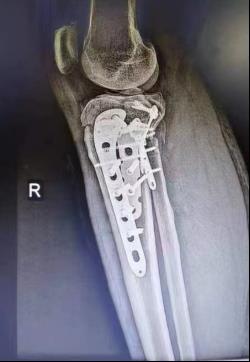

(五)胫骨平台骨折内固定术